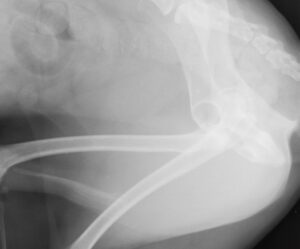

高齢の未去勢犬に多い肛門周囲腺腫

高齢の未去勢の雄犬の4大疾病は以下の4つです。 精巣腫瘍 前立腺肥大 肛門周囲腺腫 会陰ヘルニア 今回は肛門周囲腺腫のお話です。 肛門周囲腺腫は肛門の周りにしこりができます。増大することではじけて出血します。同時多発にい […]